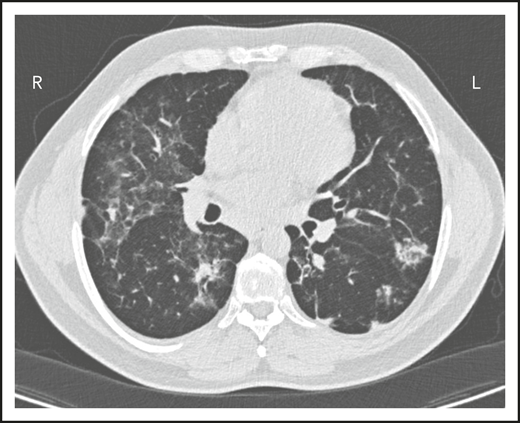

A third common reason for hematologists to see patients with CVID is a suspicion of lymphoma. Patient 3 is now a 47-year-old computer executive who came for a second opinion to the immunology department. He had had numerous sinopulmonary infections in childhood and then 2 episodes of shingles in his 30s. At the age of 36, he had acute AIHA treated with steroids. He then had an episode of cellulitis, and, with this, serum immunoglobulins were tested, which showed quite low levels: IgG, 186 mg/dL; IgA, 9 mg/dL; and IgM, 24 mg/dL. At the same time, his spleen was quite large. He was diagnosed with CVID, and immunoglobulin therapy was initiated. Owing to the enlarged spleen, now at 19 cm, a bone marrow biopsy was performed, and he was ultimately seen at another center at the age of 42, when the diagnosis of marginal zone lymphoma was made on the basis of bone marrow findings. He was treated with 6 cycles of rituximab and bendamustine. However, his splenomegaly persisted, and 3 years later, he sought an opinion at another medical center, where he was told that he did not have lymphoma on the basis of National Cancer Institute review of his bone marrow. Now, 5 years later, he has been well while receiving intravenous immunoglobulin, but he continues to have an enlarged spleen. There are no signs of lymphoma (Figure 3).

The patient in clinical case 3 was concerned because after he received chemotherapy for a presumed lymphoma, his spleen remained large. However, this is typical in patients with CVID.